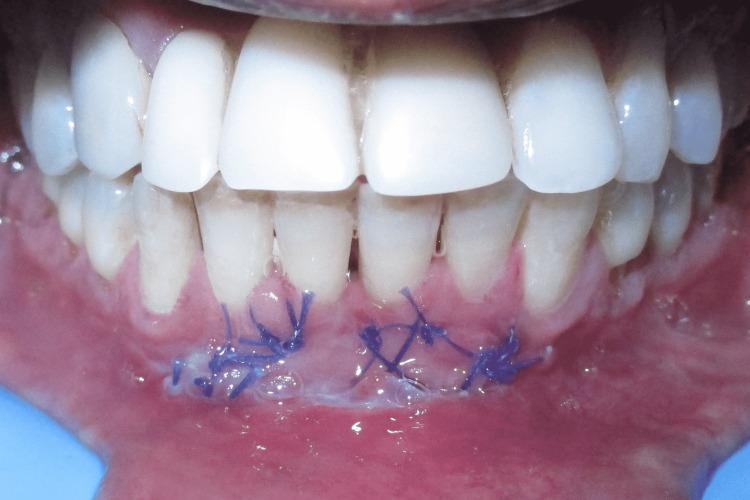

This case report describes Clark's technique of vestibuloplasty to treat shallow vestibule and, in addition, the use of free gingival autograft to augment attached gingiva to treat Miller's recession. Vestibuloplasty is performed to deepen a shallow vestibule. Different vestibuloplasty techniques are used to deepen the shallow vestibule by modifying the soft tissue attachment. A 29-year-old male presented to the Department of Periodontics and Oral Implantology, Regional Dental College, Guwahati, India with the chief complaint of bleeding from the lower anterior along with the gingival recession. Maintenance of regular oral hygiene was an added hindrance. The combined technique of vestibuloplasty and use of free gingival graft was performed to achieve dual benefits of increasing the vestibular depth and attainment of a thick gingival phenotype.

本病例报告描述了克拉克前庭成形术治疗浅前庭的技术,此外,还介绍了使用游离龈自体移植术增加附着龈以治疗米勒氏牙龈退缩的方法。前庭成形术用于加深浅前庭。通过改变软组织附着来加深浅前庭,采用了不同的前庭成形术技术。一名29岁男性因下前牙出血伴牙龈退缩,前往印度古瓦哈蒂地区牙科学院牙周病与口腔种植科就诊。保持规律的口腔卫生是一个额外的障碍。采用前庭成形术和游离龈移植术相结合的技术,以实现增加前庭深度和获得厚龈表型的双重益处。